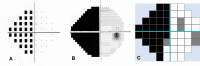

Purpose: To assess the diagnostic accuracy of visual field results generated by the newly developed software (CU-VF) and the standard automated perimetry (SAP) for detecting hemianopia.

Patients and methods: Forty-three subjects with hemianopia and 33 controls were tested with the CU-VF software on a personal computer and SAP. Hemianopia was defined as the presence of a hemianopic field respecting the vertical meridian on SAP with the corresponding neuroimaging pathology as evaluated by 2 neuro-ophthalmologists. Results of CU-VF were independently evaluated by 2 neuro-ophthalmologists, 1 general ophthalmologist, and 1 general practitioner in terms of the presence of hemianopia. Sensitivity, specificity, and kappa coefficient for inter-observer reliability were calculated. Satisfaction and ease of use were evaluated with a visual analog-scale questionnaire and analyzed using paired t-test.

Results: The sensitivity (95% CI) and specificity (95% CI) of the CU-VF to detect hemianopia was 74.42% (58.53-85.96) and 93.94% (78.38-99.94). Kappa coefficient between neuro-ophthalmologists versus general ophthalmologist and general practitioner were 0.71 and 0.84, respectively. The mean (SD) test duration was 2.25 (0.002) minutes for the CU-VF and 5.38 (1.34) minutes for SAP (p < 0.001). Subjects reported significantly higher satisfaction and comfort using the CU-VF software compared to SAP.

Conclusion: The CU-VF screening software showed good validity and reliability to detect hemianopia, with shorter test duration and higher subject satisfaction compared to SAP.